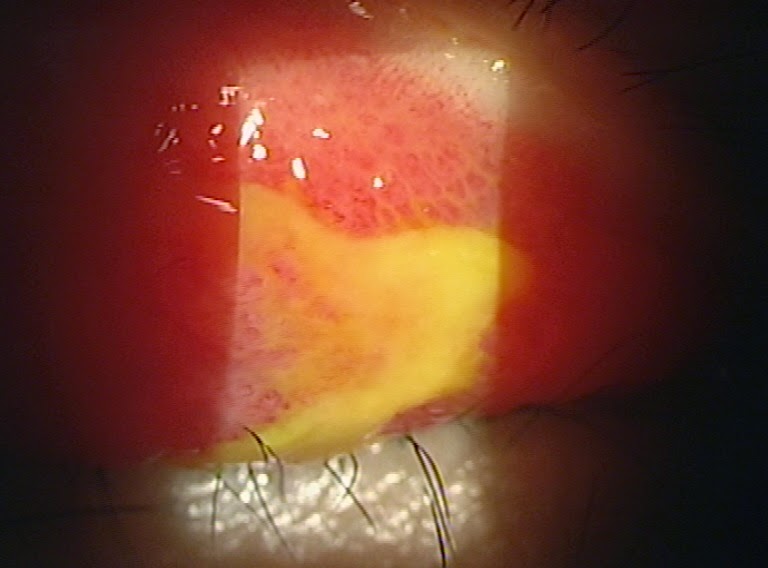

From www.sciencephoto.com

Conjunctivitis due to eyelash Stock Image C015/6012 Science Photo Can Eyelash Cause Conjunctivitis Namely, can eyelash extensions cause. If you use eyelash extensions and do not want to contract conjunctivitis, here are. Conjunctivitis is also known as red or pink eye. check if you have conjunctivitis. we are going to outline (pictures and videos) the 5 most common eye infections caused by eyelash extensions, including pink eye, styes. how can. Can Eyelash Cause Conjunctivitis.